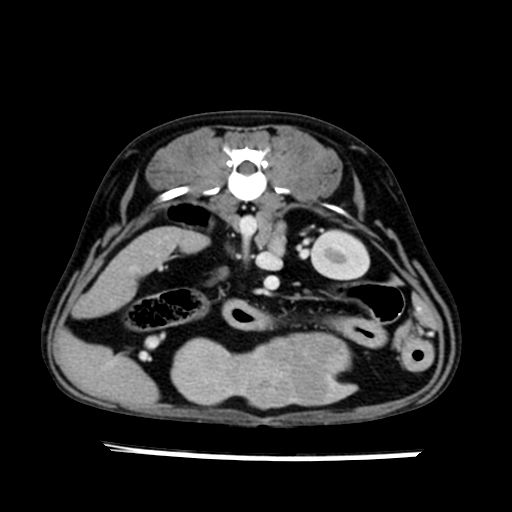

prescritto esame TAC

sequenza immagini limitata al fegato reni e surreni

le immagini ecografiche rispetto alla tac datano circa 7 mesi prima ,le surrenali sono normali nonostante il test acth sia risultato positivo .all’esame TAC dopo diversi mesi risultano aumentate armonicamente nel volume e si individua un forte sospetto di adenoma ipofisario .

sospetto adenoma ipofisario vs. meno probabilmente meningioma della base; intertiziopatia polmonare; lesione espansiva epatica, verosimilmente del lobo laterale sinistro, di sospetta natura neoplastica; lesioni spleniche di natura da definire; iperplasia/ipertrofia delle ghiandole surrenali, bilateralmente; vertebra di transizione del rachide toracico; tenosinovite cronica del muscolo bicipite brachiale di destra.